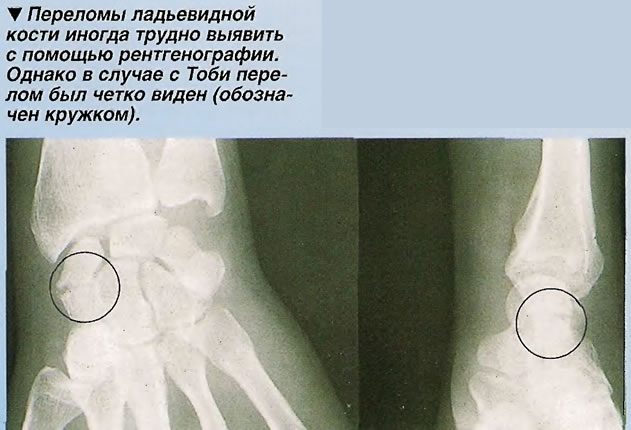

Перелом сесамовидной кости: Визуализация травмы и её лечение